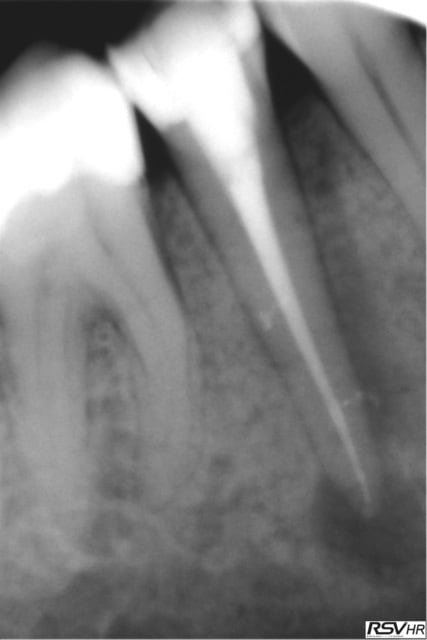

je joins un cas de traitement sur 45 ;nécrobiose,digue,hypo

1 instrument acier en cathétérisme,séquence NITI héroshaper

20%à6% puis4% 25à4% 30à4%,sealite regular,1 cône gutta fine-médium,1 compactage avec thermocompacteur(traitement

sous A.B car risques de douleurs par reprise bactérienne

Chances: des canaux secondaires obturés par le ciment

guérison de l'apex pas de douleurs pendant le compactage

cône de gutta avec "tug back" légère sensation d'échauffement

pas de douleurs post-opératoires

Un rêve....(sauf pas de HN;reconstitution SC33;sauvé par la CCM)!